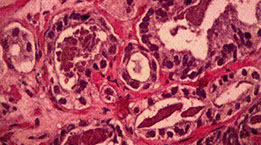

Es un exámen invasivo, con anestesia local o regional, que realiza el Urólogo cuando sospecha que puede haber un cáncer de próstata. Requiere que se realice una adecuada preparación previa. Los tejidos obtenidos, son enviados a otro médico especialista, el patólogo, para su estudio y se emita un informe, el que permitirá confirmar o descartar la sospecha.